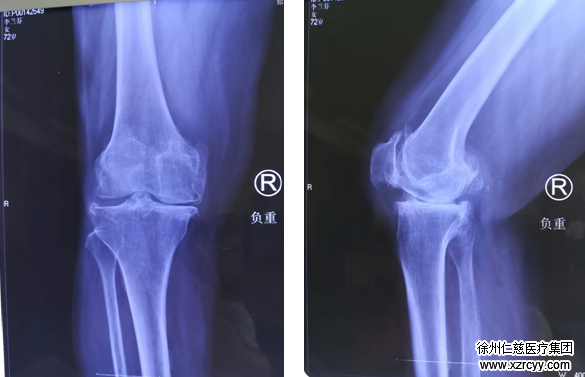

(术前检查资料)

李奶奶的主治医生、betway在线登陆关节外科医疗组长郝亮介绍,“检查发现,患者双膝关节都有畸形,其中右侧症状较重。”全膝关节置换术是李奶奶唯一能解决问题的方式。

长久以来,下肢力线一直被视作膝关节置换术的“生命线”,术中力线位置放置准确与否,极大程度上决定了患者术后的功能恢复甚至假体的寿命。然而,传统的人工膝关节置换手术需要依靠手术者的肉眼、手感和经验来判断截骨、假体位置和软组织的平衡情况,由于许多主观因素的介入,加之李奶奶膝关节畸形程度十分严重,术中力线的恢复困难重重,精准性难以保障,可能导致术后疼痛或关节活动度达不到预期。